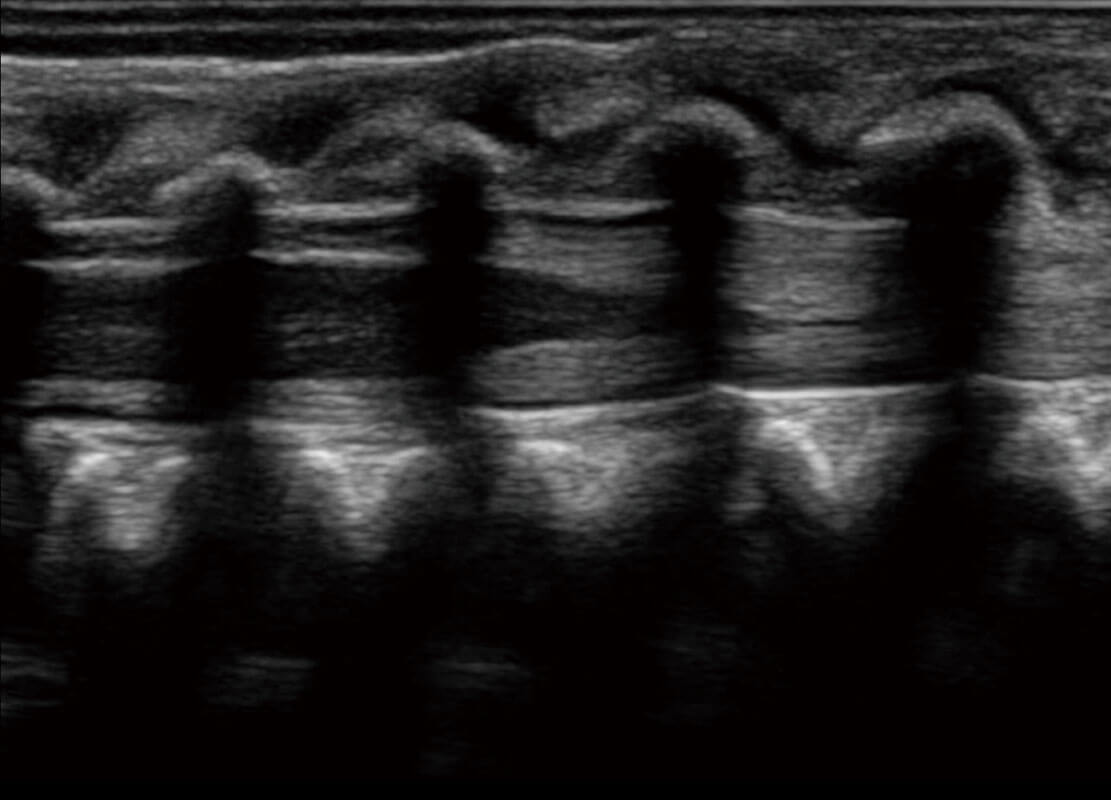

胎心筛查

P60搭载一系列胎儿心脏成像技术,实现精细的胎儿心脏评估。

• 四腔切面